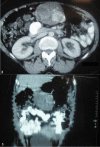

Advances in the identification of gastrointestinal stromal tumors, its molecular and immunohiostochemical basis, and its management have been a watershed in the treatment of gastrointestinal tumors. This paradigm shift occurred over the last two decades and gastrointestinal stromal tumors have now come to be understood as rare gastrointestinal tract tumors with predictable behavior and outcome, replacing the older terminologies like leiomyoma, schwannoma or leiomyosarcoma. This report presents a case of gastric gastrointestinal stromal tumor operated recently in a 47-year-old female patient and the outcome, as well as literature review of the pathological identification, sites of origin, and factors predicting its behavior, prognosis and treatment.